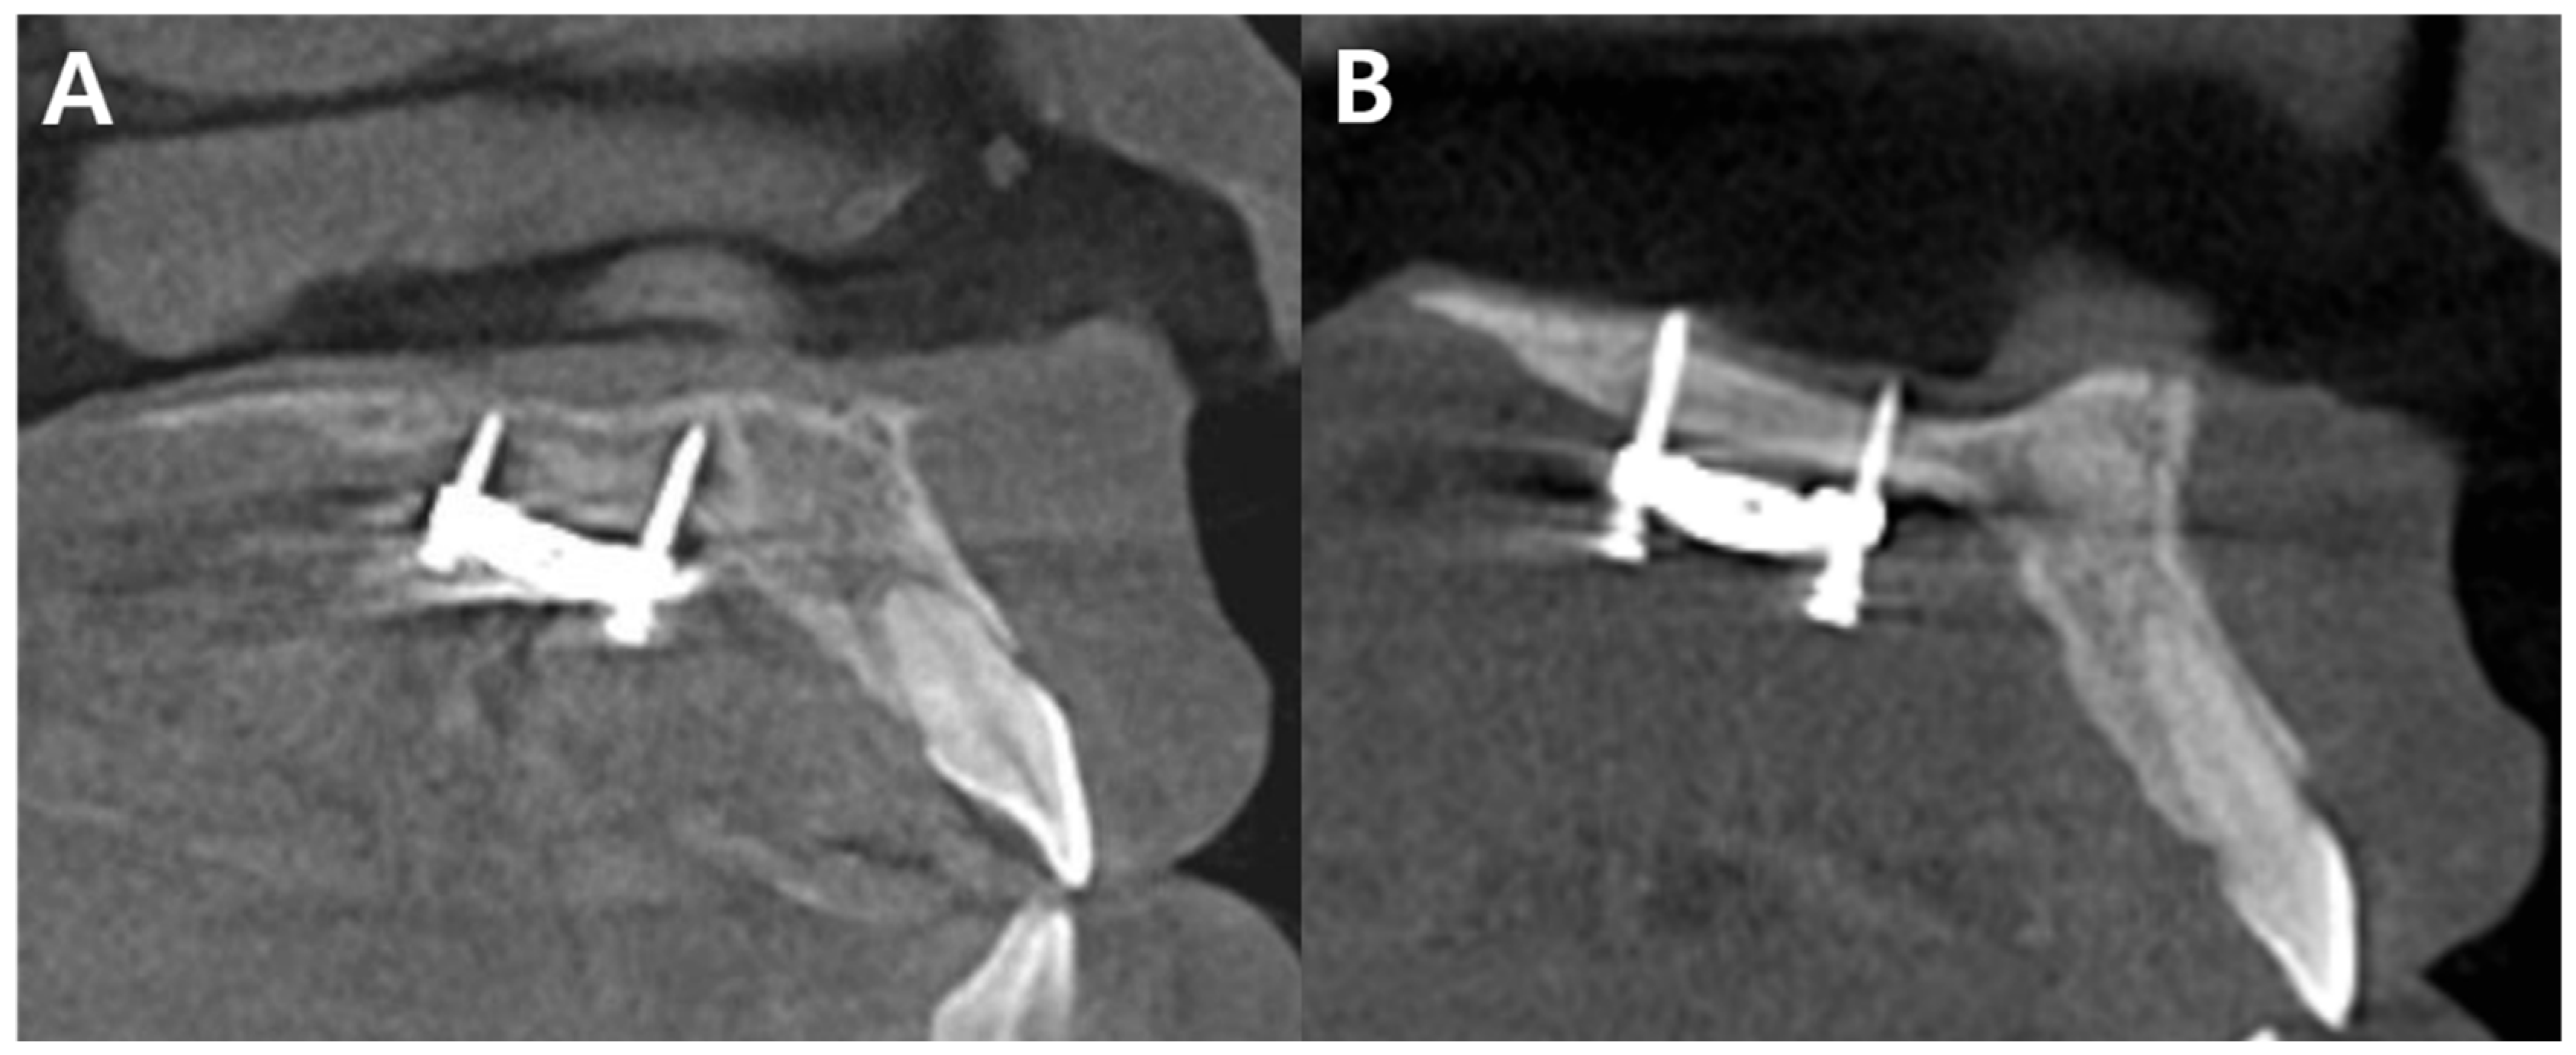

- Carlson, C.; Sung, J.; McComb, R.W.; Machado, A.W.; Moon, W. Microimplant-assisted rapid palatal expansion appliance to orthopedically correct transverse maxillary deficiency in an adult. Am. J. Orthod. Dentofac. Orthop. 2016, 149, 716–728. [Google Scholar] [CrossRef]